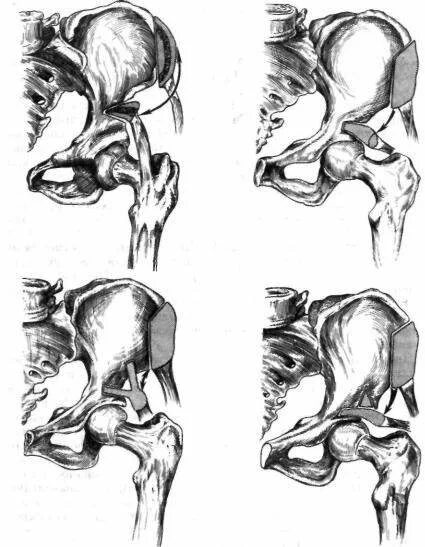

Вывих тазобедренного у взрослых